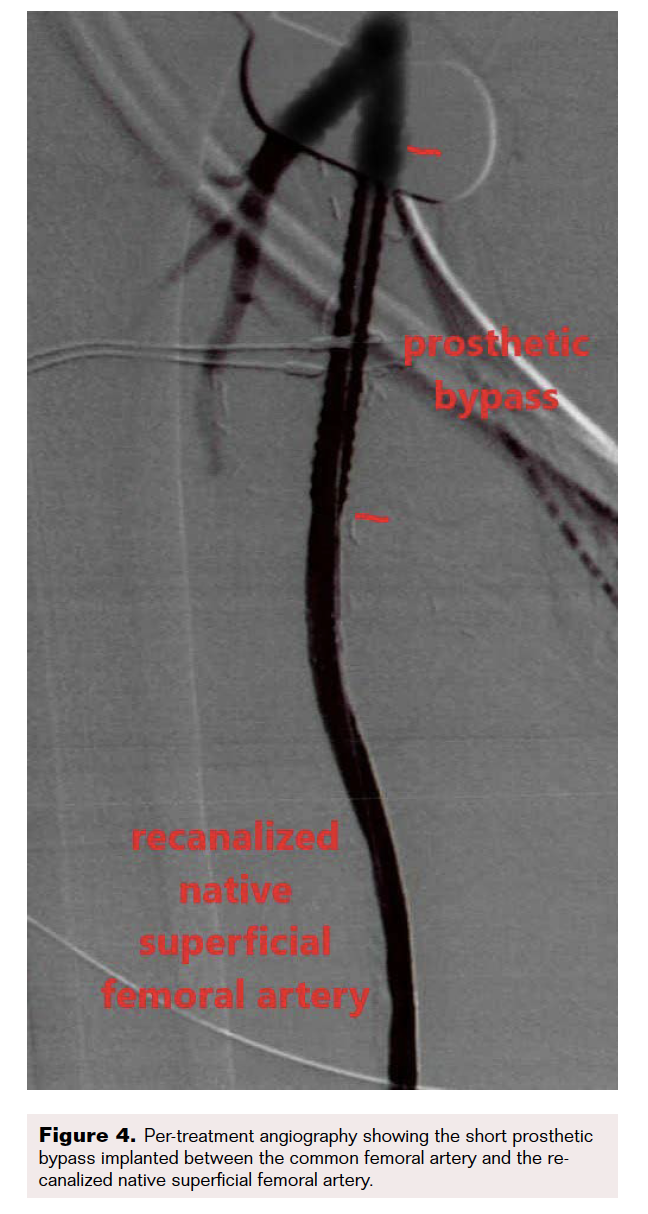

Computed tomography angiography highlighted thrombosis of the femoroposterior tibial bypass and a grade 4 Global Limb Anatomic Staging System femoropopliteal and tibioperoneal trunk chronic total occlusion (CTO). Runoff vessels were patent (Figure 2). Through retrograde posterior tibial puncture, we tried to recanalize the CTO but were not able to get into the common femoral artery (CFA) because the SFA ostium was ligated (Figure 3). We performed a short Dacron prosthetic bypass between the CFA and the proximal part of the SFA (Figure 4), followed by stenting of the whole SFA and the proximal third of the popliteal artery with drug-eluting stents. The distal part of the popliteal artery and the tibioperoneal trunk were treated with balloon angioplasty.